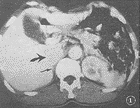

图1 良性功能性副节瘤 CT强化扫描示肾上区肿块(大箭头)轻强化,右侧肾上腺存在(小黑箭头)

2.2 病变数目:本组14例均为单发,未见多发。其中呈团块结节者10例(图1,2,5,6),呈连续长块状4例(图4)。

2.3 病变大小:病变最大径<5 cm者6例(图1,2,5,6),其中良性5例,恶性1例;功能性5例,非功能性1例。病变5~10 cm者5例(图3),其中良性4例,恶性1例;功能性1例,非功能性4例。病变>10 cm者3例(图4),均为恶性;功能性1例,非功能性2例。

2.4 病变形态:病变边缘呈光滑圆形结节状3例,均为良性(图1,2,6),有不同程度分叶切迹,或呈分叶不规则状11例(图3,4,5)。

2.7 病变质地:病变密度或信号强度呈均匀者7例(图1,5),不均匀者2例(图2),有明显坏死囊变者5例(图3,4),其中1例有小点钙化。伴有坏死囊变者5例中4例为恶性,1例为良性。

2.8 病变强化特点:5例进行CT强化扫描均表现肿瘤周边部明显强化(图6),其中3例肿瘤内部见不规则强化,2例良性(图2),1例为恶性(图4)。